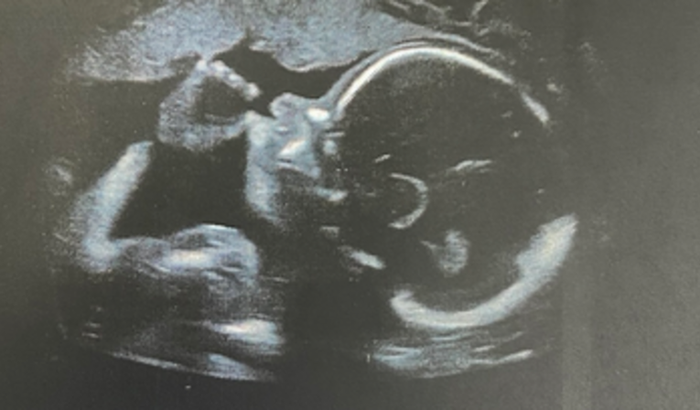

Meu nome é Kerolen e estou grávida de 27 semanas da Cecília.

Com 24 semanas ela foi diagnosticada com hidrocefalia isolada severa e existe uma cirurgia chamada terceiro ventriculostomia para desubistruir o ventrículo e esse líquido que está se acumulando na cabeça dela ser drenado corretamente pelo corpo.